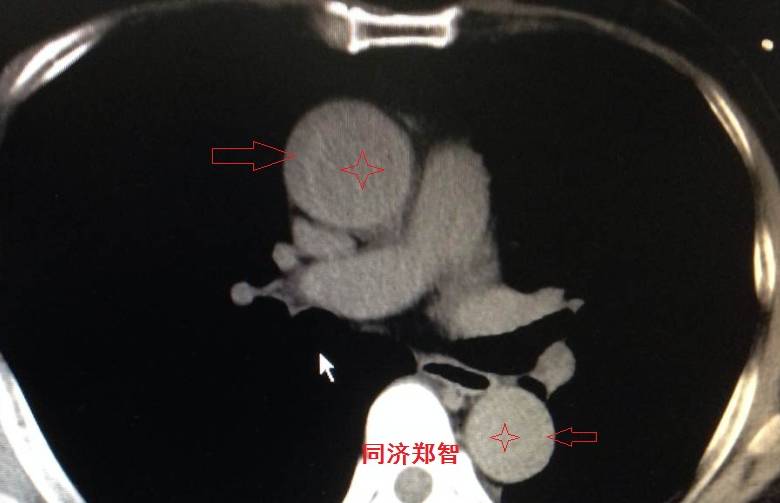

病例四

腹部平扫CT提示腹主动脉增宽,CTA证实为腹主动脉局限性夹层(红箭头所示)